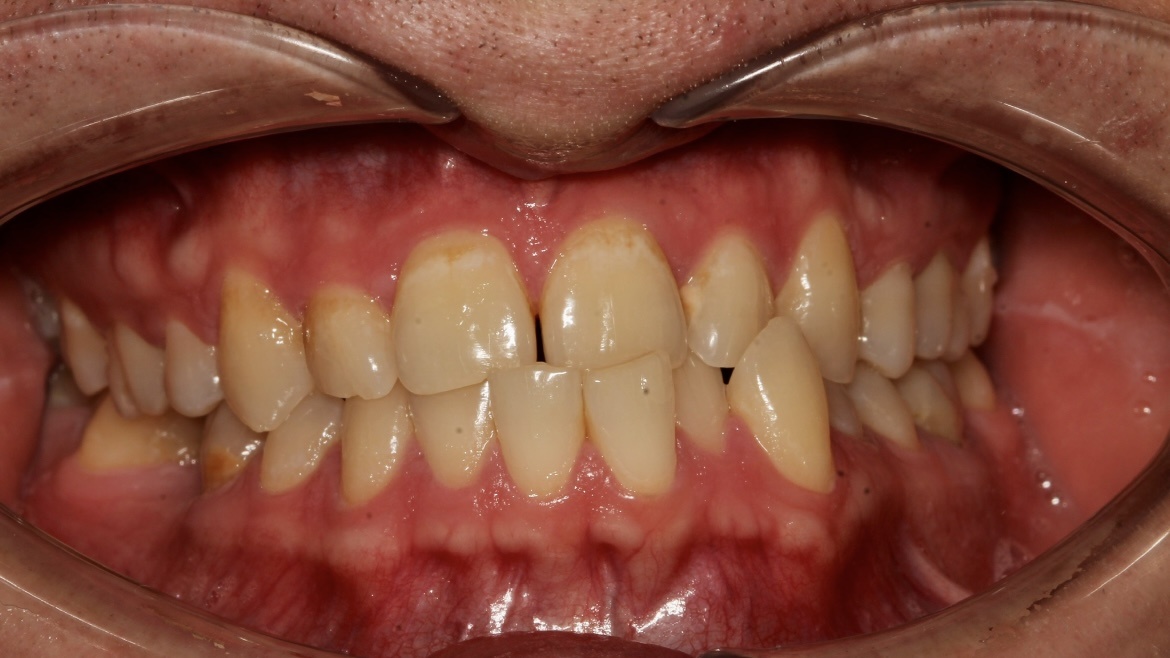

Пациент обратился в клинику «Два Дантиста» для восстановления эстетики зубов. Результат лечения его клинического случая — это совместная работа врача и пациента.

Джексенбаева Зарина Касымкановна, стоматолог-ортодонт, провела пациенту ортодонтическое лечение на элайнерах с использованием одного минивинта. Лечение длилось 2,5 года. По итогу получилось исправить прикус, скученность зубов, нормализовать контакты между верхней и нижней челюсти.

Также пациенту установили имплантат в месте отсутствующего зуба, на который Лукьяненко Артур Викторович, стоматолог-ортопед, зафиксировал керамическую коронку, восстановив целостность зубного ряда.

Кожокарь Карина Васильевна, стоматолог-терапевт, реставратор, с помощью композитного материала сделала реставрацию стертых единиц. Она нарастила края зубов, тем самым вернула единицам красивую и органичную форму.